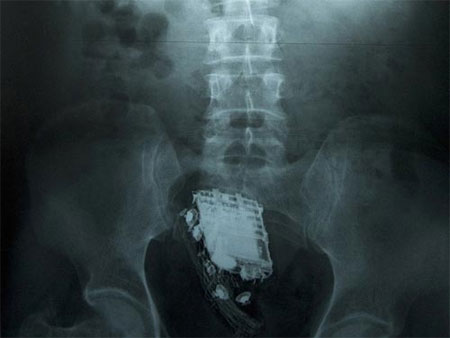

Default Hy hữu chuyện điện thoại kẹt vào "chỗ kín"

Roderick Bambury, một tù nhân đang bị giam giữ tại nhà tù Perth Prison, một trong những nhà tù được canh pḥng nghiêm ngặt nhất tại Scotland, đă lâm vào t́nh trạng “dở khóc dở cười”, sau khi cố gắng nhét một chiếc điện thoại di động vào hậu môn với hy vọng có thể mang vào buồng giam nhưng lại không thể lấy chiếc điện thoại này ra ngoài.

Bambury sau đó đă phải trải qua một ca phẫu thuật khẩn cấp để lấy chiếc điện thoại di động ra khỏi cơ thể của ḿnh.

Quy định của nhà tù Perth Prison là không cho phép các phạm nhân mang thiết bị liên lạc vào bên trong buồng giam. Tuy nhiên, tù nhân 36 tuổi đến từ thành phố Dundee (Scotland) thừa nhận đă sử dụng “mánh khóe” này để qua mặt các lính canh của trại giam và mang điện thoại di động vào buồng giam của ḿnh từ tháng 6 năm ngoái.

Sau khi bị phát hiện hành vi gian lận, Bambury đă bị kết án tăng thêm 4 tháng rưỡi tù giam so với bản án phạt ban đầu.

Tuy nhiên, Bambury cũng đă rất “tử tế” khi gửi lời cám ơn đến đội ngũ bác sĩ đă giúp y thoát khỏi t́nh trạng khó chịu khi lấy chiếc điện thoại ra khỏi cơ thể, đồng thời chấp nhận án phạt tăng thêm dành cho ḿnh mà không kháng cáo.